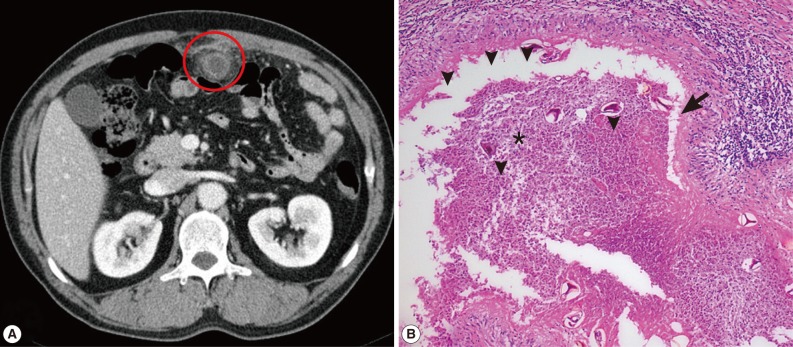

3 with no other abnormal laboratory findings. Chest X-ray was normal and abdominal computed tomography (CT) showed a ring-shaped mass lesion, with focal irregular enhancement in the omentum (

Fig. 1A). We suspected non-specific intra-abdominal abscess and performed exploratory laparotomy. During the surgery, a 3×2 cm sized mass was recognized in the omentum. Omentectomy for the omental abscess and adjacent small bowel resection were done. Microscopic pathologic examinations revealed the eggs of

P. westermani scattered with acute suppurative inflammation and foreign body-type giant cells (

Fig. 1B). A retrospective history taking showed that he had frequently consumed 'Kejang' (drunken crab), which was prepared using freshwater crabs. The treatment decided for the patient was praziquantel (25 mg/kg, 3 times daily for 2 days), and the patient recovered uneventfully.

Fig. 1CT and microscopic findings of omental paragonimiasis. (A) Abdominal CT showed ring-shaped mass lesion with focal irregular enhancement in the omentum (red circle). (B) Microscopic pathologic examinations revealed the eggs of P. westermani (arrowheads) scattered with acute suppurative inflammations (star) and foreign body-type giant cells (arrow). H&E stain, ×100.